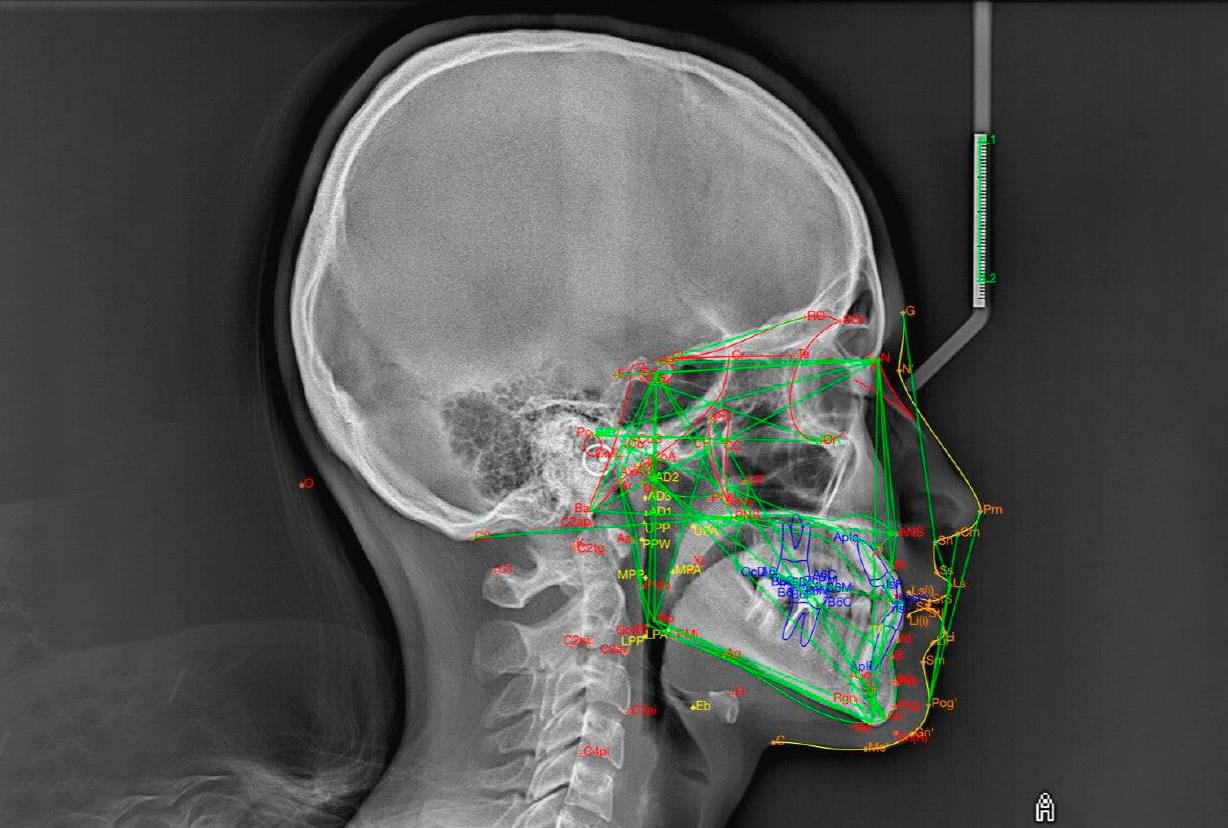

Це окрема діагностична послуга, під час якої лікар-діагност оцифровує знімок, розставляє анатомічні точки та вимірює кути і відстані між кістками черепа та зубами.